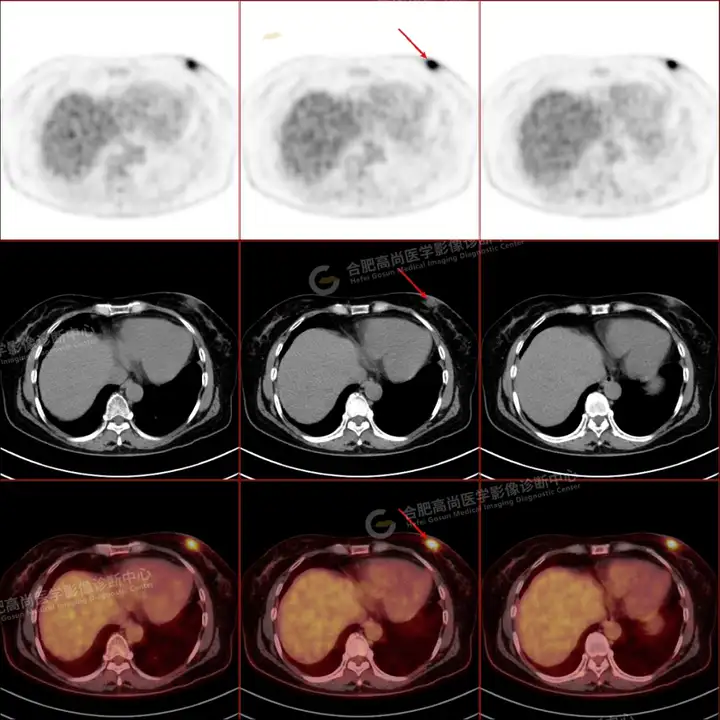

PETCT检查所示:图1、3-17全身多处(双上臂、胸背部、左侧乳腺、左侧腰部、腹壁、双侧臀部及双侧大腿)皮肤下结节及肿块样软组织密度灶,FDG代谢不同程度增高,双侧颈部、左侧锁骨区、纵隔内(1区)及双侧腋窝多发肿大淋巴结,FDG代谢明显增高,符合皮肤来源淋巴瘤。